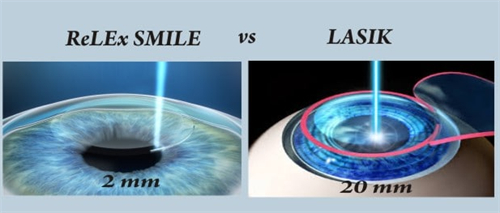

全飞秒激光手术:15800元/双眼

激光手术价格持平

近视手术下调约5%(设备升级后)